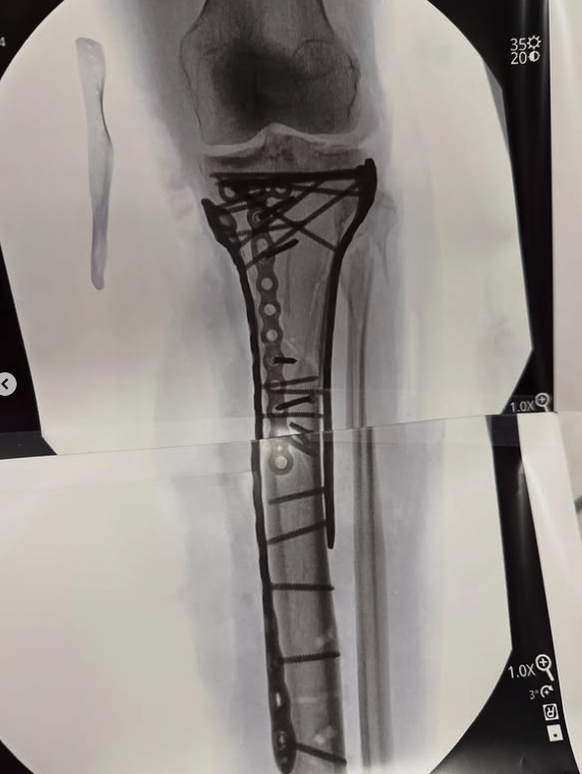

Vonn schwärmt von der Leistung ihrer Ärzte. «Dr. Hackett hat unglaubliche Arbeit geleistet. Danke Dr. Viola auch für die OP-Assistenz», schrieb die 41-Jährige. Im geteilten Beitrag veröffentlichte Vonn auch Fotos von ihrem verletzten Bein. «Wie man sieht, benötigt es viele Platten und Schrauben, um das Bein wieder zusammenzubringen», kommentierte Vonn den Beitrag.